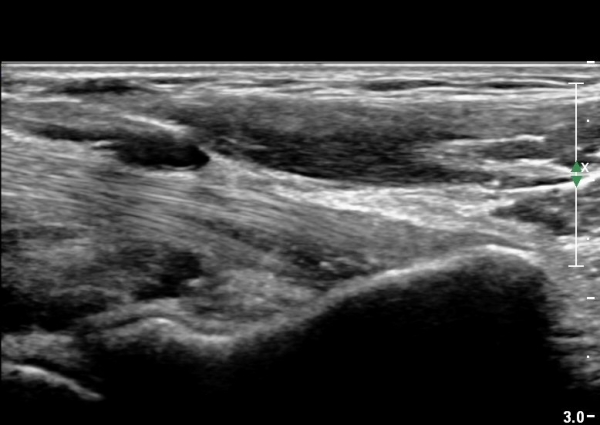

Á¶±Ý ´õ ¸»´ÜÀ¸·Î À̵¿ÇÏ¿© °üÂûÇÏ´Ï ÀÌµÎ¹Ú±Ù°Ç ½ÇÁú³» ÆÄ¿­°ú °üÀý ÁÖÀ§ ¼ö¾×Àú·ù°¡ °üÂûµÊ(±×¸² 4, 5).

ÀÌµÎ¹Ú±Ù°Ç Á¾´Ü¸é°Ë»ç¿¡¼­ ÀÌµÎ¹Ú±Ù°Ç ºÎÂøºÎ ¿ä°ñµ¹±âÀÇ ºñÈÄ¿Í À̵ιڱٰÇÀÇ Á¾¹æÇâ ÆÄ¿­ ¹×

ºÎÁ¾ÀÌ °üÂûµÊ(»çÁø 6, 7).